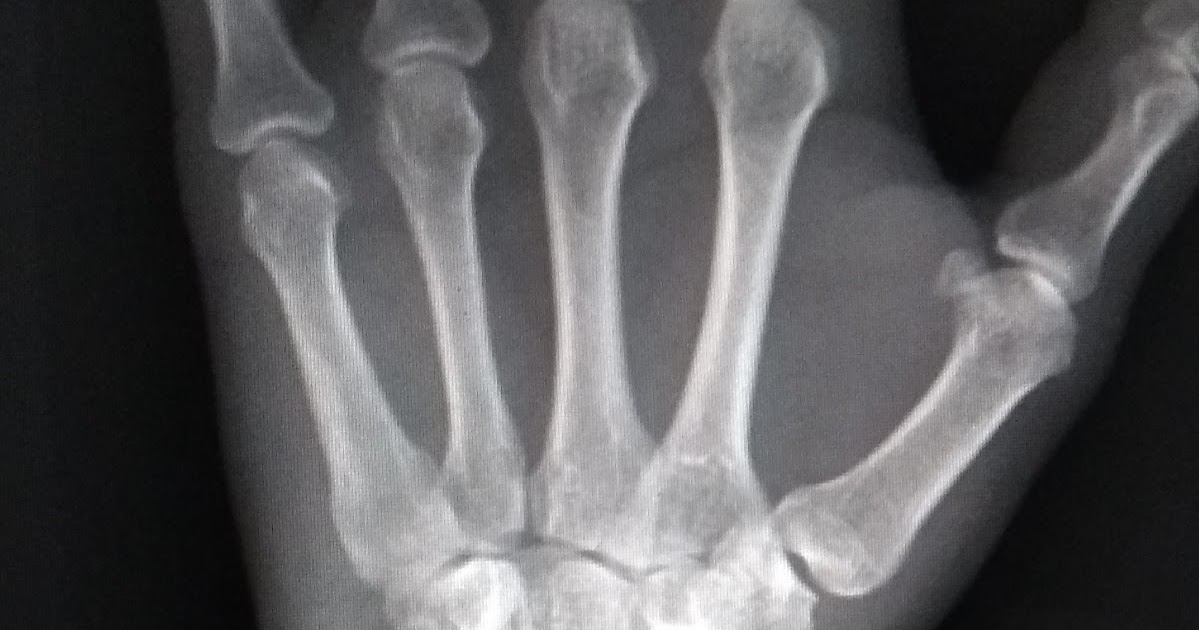

A fratura de rádio distal é uma das mais prevalentes entre as fraturas de punho, ocorrendo principalmente em casos de trauma de alta energia, em indivíduos jovens, e baixa energia, em idosos, em que o indivíduo cai no chão com a mão espalmada. Trata-se de um problema relativamente comum em crianças, especialmente em decorrência de.. Em geral, as fraturas da cabeça do rádio resultam de queda sobre o membro superior em extensão, e podem ser difíceis de ver nas radiografias. (Ver também Visão geral das fraturas .) A cabeça do rádio é palpável na porção lateral do cotovelo como uma estrutura que se rotaciona durante pronação e supinação e que se articula com o.